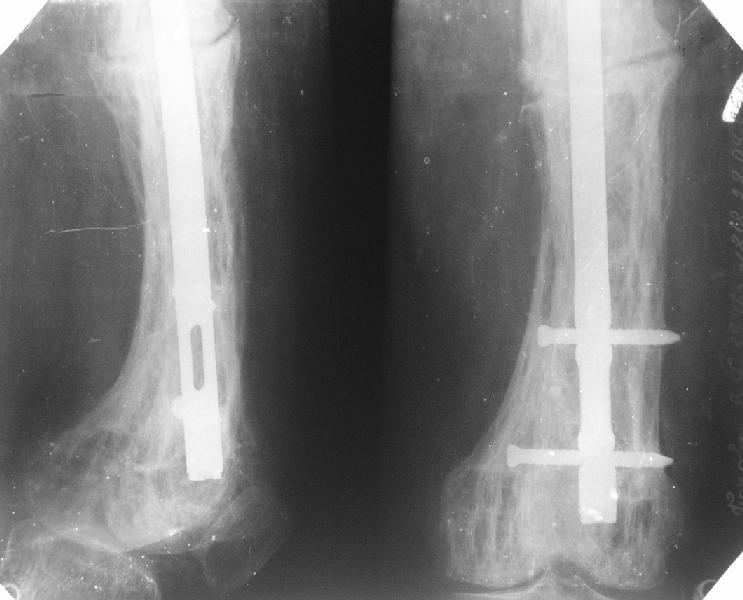

Еще один пример. Пациентка с юга России, прислала рентгенограммы через год. На сегодня прошло 2 г. 8 мес. после операции. Несмотря на не очень убедительный процесс сращения, пациентка ходит. Учитывая остеопороз при Педжете, решили, что динамизировать вообще не нужно.